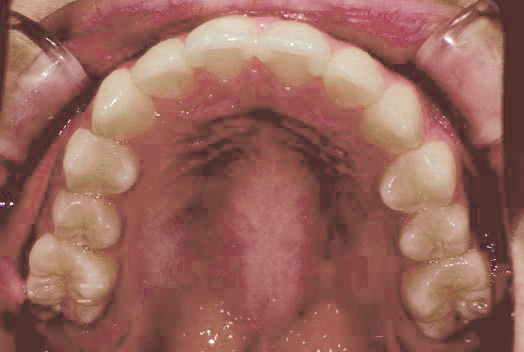

Before

After

上あごの成長が少なく、特に前歯のガタガタが目立っていました。口呼吸のクセや飲み込み方に良くないクセが確認されました。

治療を終えて

マイオブレイスとBB1装置で上あごの成長を助け、鼻呼吸や正しい飲み込み方を身につけることで、きれいな歯並びとしっかり噛めるお口に変わっていきました。

姿勢やお口の機能を正しく整えたので、後戻りしない綺麗な歯並びを維持できています。もちろん非抜歯です。

主訴・治療内容 当院と交流のある歯科医師の先生が、ご自身のお子さまの治療を任せてくださいました。

「難しい歯並びでも永久歯を抜かず、全身の健康と顔立ちも考えて治療してくれる」と信頼していただいて治療開始。

治療期間 3年

費用 462,000円(税込)

リスク・副作用

• 治療の初期段階では、痛みや不快感が生じやすくなりますが、一週間前後で慣れます。

• 歯の動き方には個人差があるため、予想された治療期間より延長する場合があります。